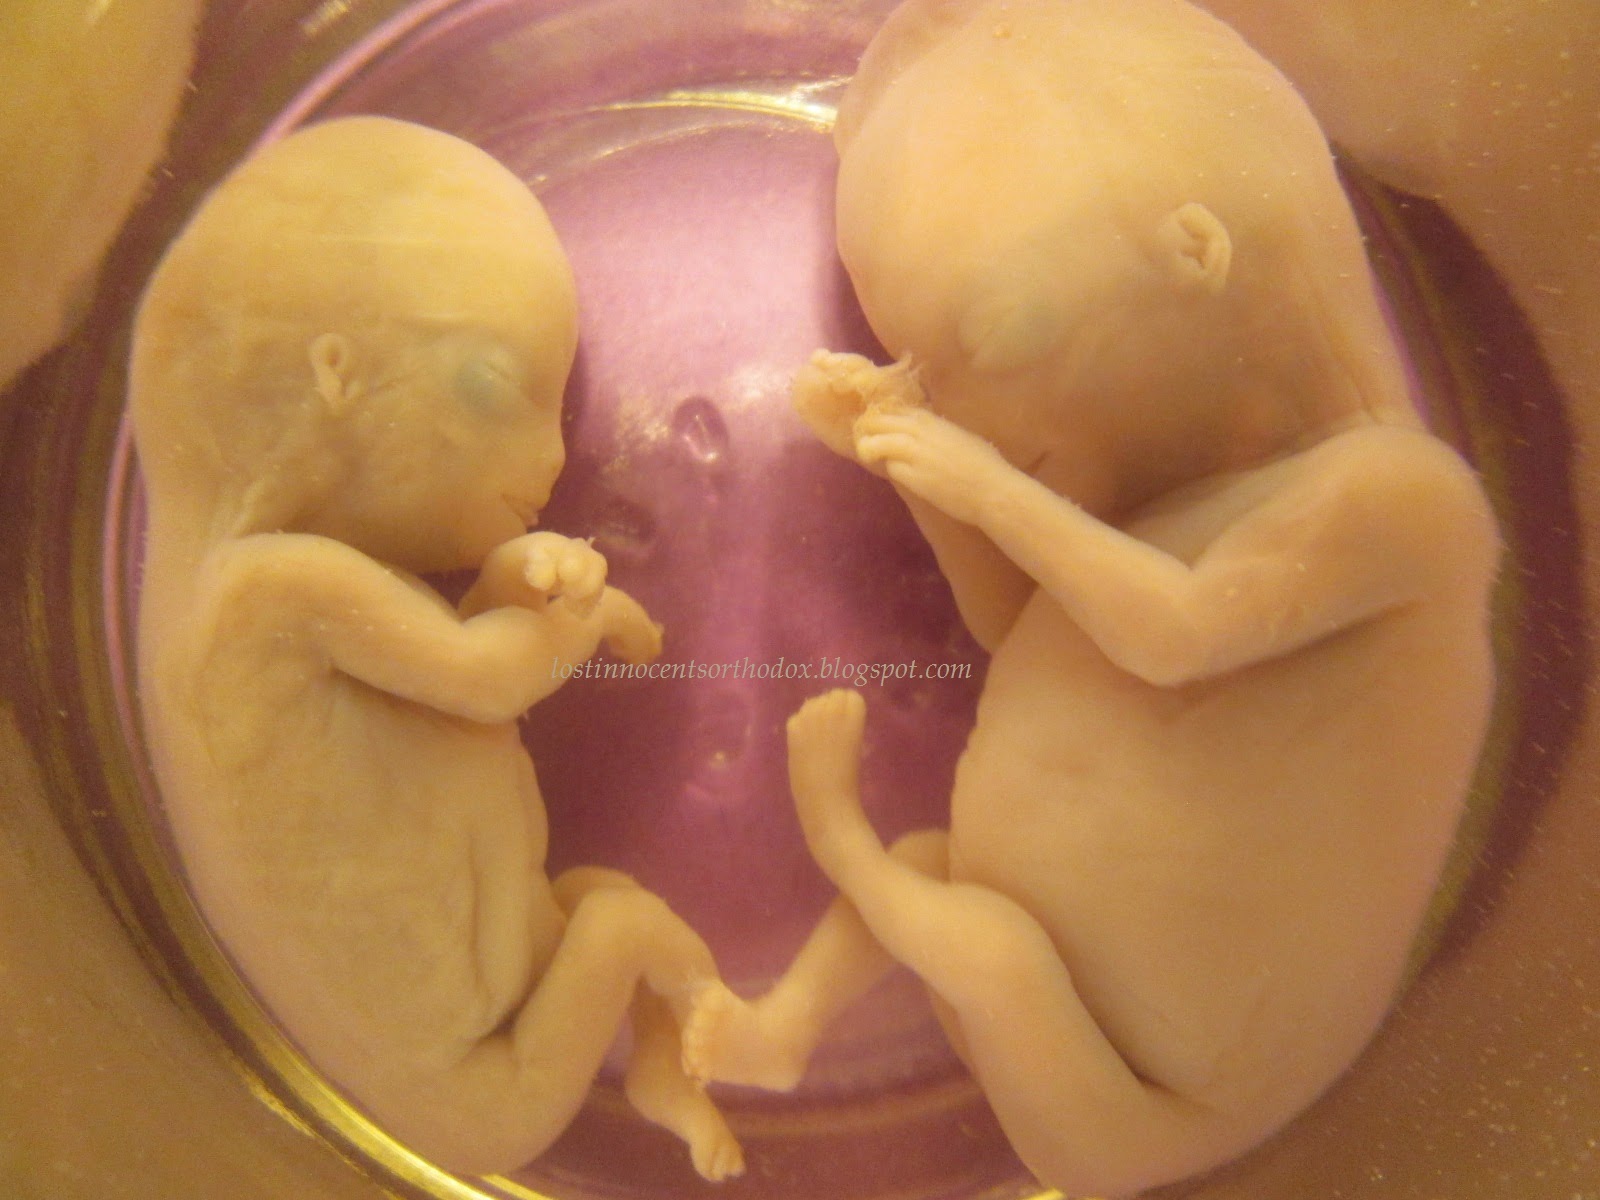

Heavenly’s baby, Arrow (11 weeks)

Arrow is one of a set of twins, his sibling being 5 weeks (see above under 5 weeks heading). They were born after expectant management.

Cedar is one of a set of twins, his sibling being 11 weeks (see below under 11 weeks heading). They were born after expectant management.

Heavenly’s baby, Cedar (5 weeks, shown in sac)